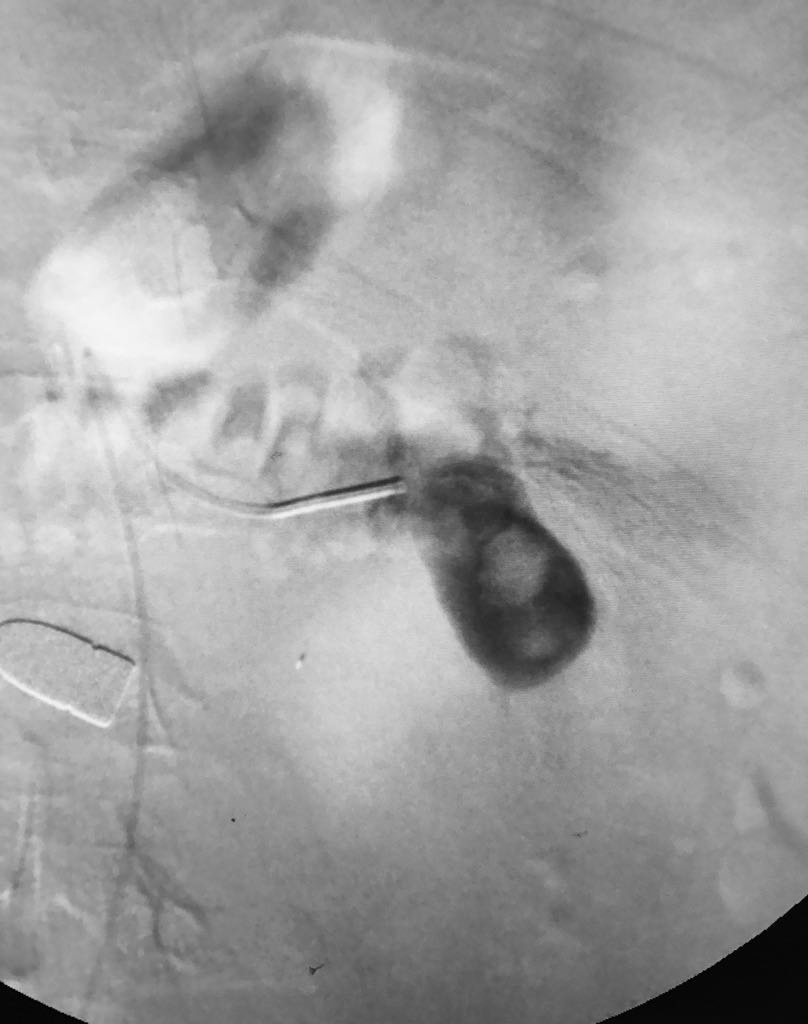

Somos una empresa enfocada en la atención en salud humana por medio del uso imágenes para ver diagnosticos y tratamientos de las diversas patologías con el uso de técnicas mínimamente invasivas en el territorio colombiano en el sector público y privado en búsqueda de una atención oportuna y de calidad a cada uno de nuestros pacientes.